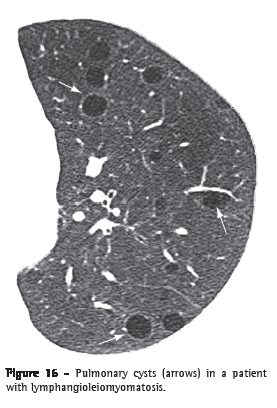

Cyst (cisto)A cyst is any rounded, well-circumscribed space surrounded by an epithelial or fibrous wall of variable thickness.(29) On CT scans, a cyst is seen as a rounded area with low attenuation coefficient on the lung parenchyma, having a well-defined interface with the adjacent normal lung (Figure 16).(1,7) The cyst wall is usually thin (< 2 mm), but it can vary in thickness. Cysts are usually filled with air but can also contain liquid (e.g., bronchogenic cyst) or even a solid material. Diseases accompanied by multiple pulmonary cysts include lymphangioleiomyomatosis, Langerhans cell histiocytosis, lymphocytic interstitial pneumonia and Birt-Hogg-Dubé syndrome.(30,31)